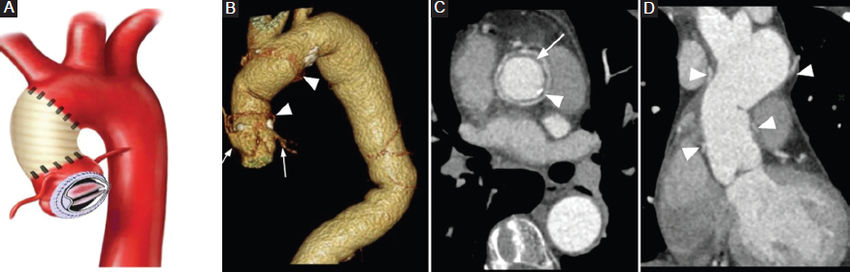

Cirugía de Wheat

El empleo de un injerto aórtico ascendente que se coloca distal al ostium de las arterias coronarias se conoce como injerto supracoronario, y al asociarse con un reemplazo de la válvula aórtica se conoce como técnica de Wheat (Fig. 1). Los injertos supracoronarios se indican en pacientes con aneurisma de aorta torácica ascendente (generalmente de origen aterosclerótico) que presentan indemnidad estructural de los senos de Valsalva. Con este procedimiento se evitan las complicaciones de la manipulación del ostium coronario nativo, lo cual se traduce en una minimización de los riesgos de pseudoaneurismas, estenosis, trombosis y pliegues en el sitio de la anastomosis coronaria. Las complicaciones más frecuentes de este procedimiento son la disección aórtica nativa proximal y los pseudoaneurismas2,3,4.